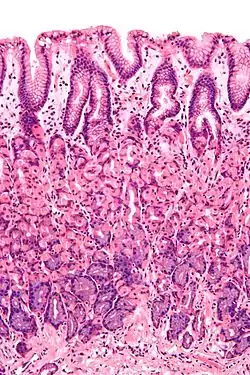

Simple columnar epithelium is a single layer of columnar epithelial cells which are tall and slender with oval-shaped nuclei located in the basal region, attached to the basement membrane. In humans, simple columnar epithelium lines most organs of the digestive tract including the stomach, and intestines. Simple columnar epithelium also lines the uterus.

Simple columnar epithelium is further divided into two categories: ciliated and non-ciliated (glandular). The ciliated part of the simple columnar epithelium has tiny hairs which help move mucus and other substances up the respiratory tract.

The shape of the simple columnar epithelium cells are tall and narrow giving a column like appearance. the apical surfaces of the tissue face the lumen of organs while the basal side faces the basement membrane.[1] The nuclei are located closer along the basal side of the cell.[1]

Absorptive columnar epithelium is characterized as having a striated border on its apical side, this border is made up of non-motile microvilli allowing for increase surface area for absorption.[1] These are known as non-ciliated columnar epithelium. Non-ciliated simple columnar epithelium is made up of glandular goblet cells which secrete mucin to form mucus.[1] The rest of the cell is made up of cytoplasm with membrane bound secretory granules which secrete the mucin, and are found towards the apical surface of the cell.[1]

These are found in the lining sections of the gastrointestinal tract (inner lining of oesophagus, stomach, etc.) and may be brush bordered.